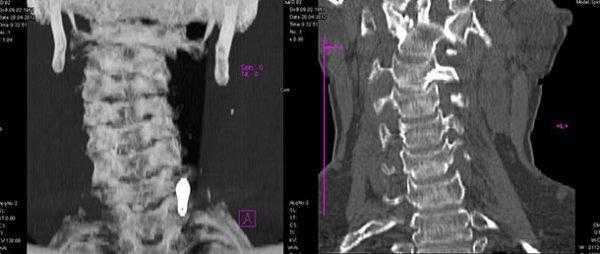

КТ головы и шеи. Нарушение соотношения зубовидного отростка осевого позвонка (красная стрелка) и передней дуги атланта (синяя стрелка).

На КТ позвоночника выявляется уменьшение высоты диска и смещение суставных поверхностей, а при подвывихе С1 - асимметрия между атлантом и зубом. Проведение МРТ позвоночника позволяет уточнить состояние мягких тканей. Кроме того, пациентам с подозрением на подвывих позвонков назначают консультацию невролога для выявления возможных неврологических нарушений. При застарелых подвывихах и подозрении на ухудшение кровоснабжения головного мозга показана реоэнцефалография.

КТ головы и шеи (этот же пациент). Подвывих в срединном атланто-аксиальном суставе, зубовидный отросток (красная стрелка) смещен вправо.